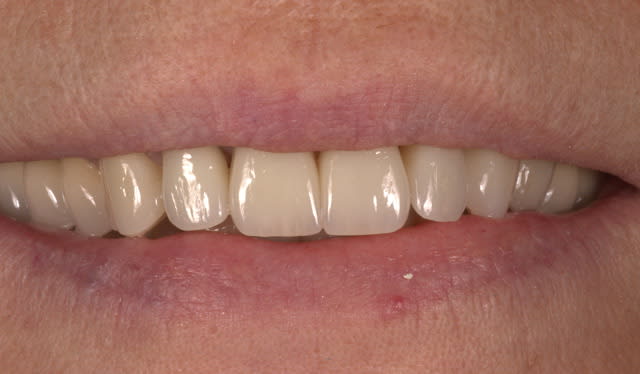

mon cas de renamel microfill

pas aussi réussi que le tien

la différence c'est que mon patient est content !

Belle morpho, bien vue la caractérisation "milky", il y a un souci en profondeur 1 à 2 teinte trop sombre: soit joint de colle trop épais, soit choix de composite trop foncé (UD4 ici peut être).

oui, tu as tout à fait raison, je me suis chié sur le choix de la dentine, trop sombre

pareil, j'ai mis de l'ambre sur le bord libre alors que j'aurais du mettre un truc blanc